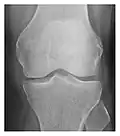

- a

- b

- c

Figure 1: A 56-year-old woman presenting with left knee pain after a fall. (a) Initial anteroposterior radiograph was considered normal, however, subtle cortical disruption of the anterior rim of the medial tibial plateau, medial to the tibial spine, is noted (arrow). (b) Coronal T1-weighted MRI confirms the cortical disruption (arrow) and shows extensive fracture through the proximal tibia. (c) Coronal proton density-weighted image with fat saturation shows extensive edema in the subchondral bone. Note also hypersignal adjacent to the medial collateral ligament corresponding to a grade I sprain (arrowheads).[1]